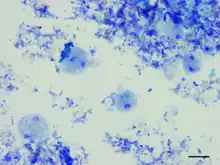

Dientamoeba fragilis, in a specimen prepared using the Kohn stain | |